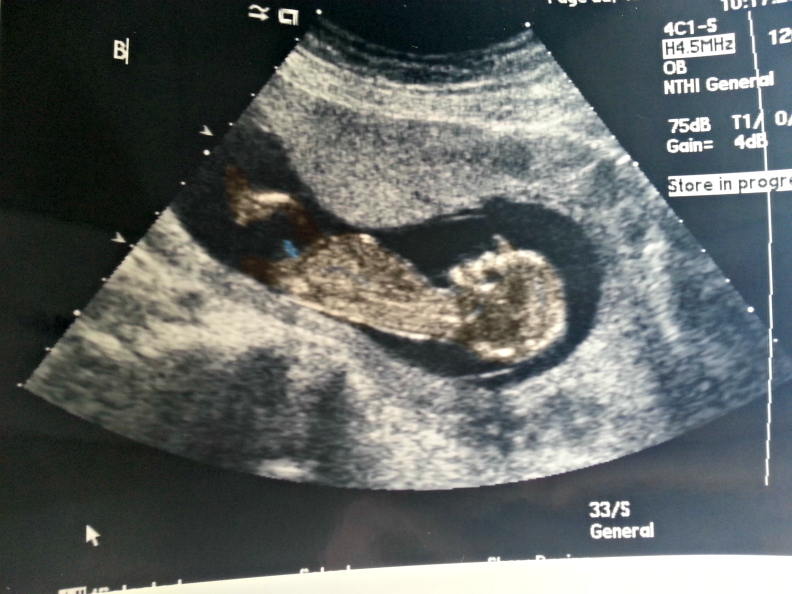

13 weejs 4 days, Not sure how big the babies are measuring because I forgot to ask :/. Babies were extremely active and doing lots of flips and kept turning their backs to the tech already causing trouble lol!

Attachment 23537

Attachment 23538

Attachment 23539

Attachment 23540

Attachment 23541

Attachment 23542

Awww cuties! Gosh how cool it would be if they are both girls! I personally would love that sooooo much! Can't wait to hear :)